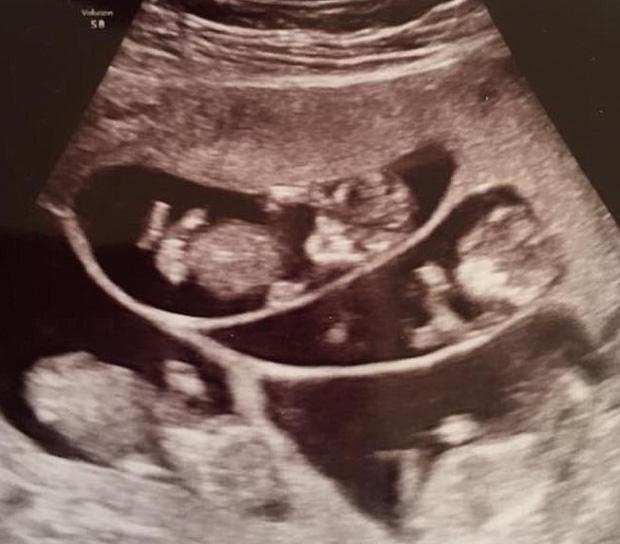

Cứ thế cặp đôi đều đặn đến viện thăm khám để đảm bảo sức khoẻ cho cả hai mẹ con. Rồi ngày định mệnh ấy cũng đến, hôm đó, cặp đôi có mặt để siêu âm như thường lệ thì bác sĩ thông báo trong bụng Bobbi không phải có một phôi thai mà có tận... 7 cái.

Khỏi cần nói, không chỉ cặp đôi mà các bác sĩ, gia đình bạn bè của họ, ai cũng không dám tin vào những gì mình nghe được. Chưa dừng lại ở đó, họ cùng lúc phải đón nhận một tin buồn khác chính là việc mang thai 7 có nguy cơ cao ảnh hưởng đến sức khỏe của các em bé và chính Bobbi, thậm chí nó có thể lấy đi mạng sống của họ.

Hình ảnh siêu âm thai 7 của Bobbi.